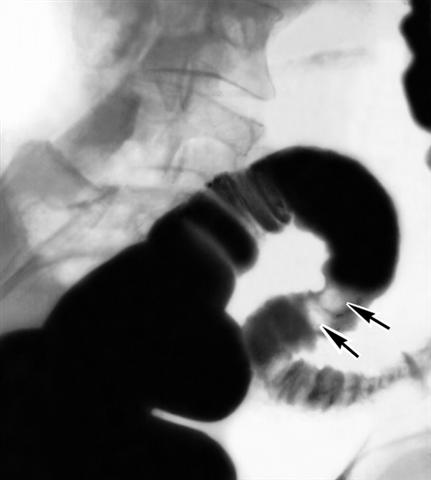

Рис. 3. Рентгенограмма сигмовидной ободочной кишки при полипозе (стрелками указаны дефекты наполнения).